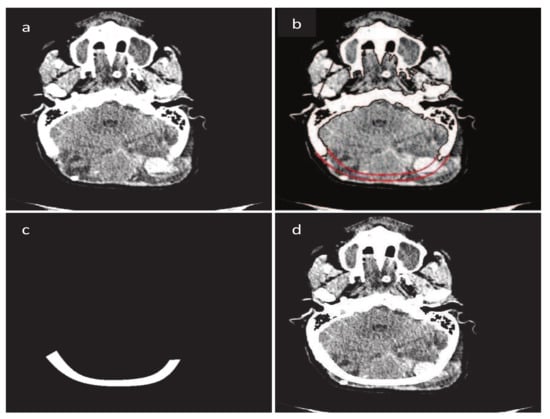

Figure 8. Construction of fractured part using B-spline. (a) Original CT scan image; (b) Construction of fractured part boundary curves; (c) Fractured part in DICOM format; (d) Implanted fractured part.

for j = 0 , , m and n 1 . These bases have been used for the construction of the occipital bone fracture by [12]. The reconstructed occipital fracture is shown in Figure 8.

To reduce the number of control points and overcome the computational cost, cubic B-spline is used to restore the cranial implant. It is very user friendly, one can get the desired curve just clicking on the CT scan image and there is no need to tackle shape parameters, as shown in Figure 20. Using the B-spline curve, there is no need to define and generate the continuity condition between two segments, in contrast to G C 1 and G C 2 where the continuity has to be generated. The main controlling tool in the B-spline curve is the knot points; one can change and adjust the curve using knot points. In order to make more flexible and smooth NURBS curves, it has been used for fracture reconstruction, as shown in Figure 21. The NURBS curve is a modified form of the B-spline and is more flexible due to the presence of weights.